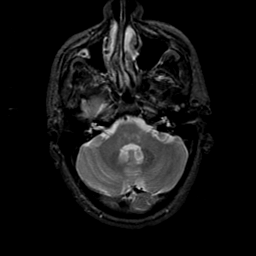

MR Study #23, January 26, 1992 -- Slice #11